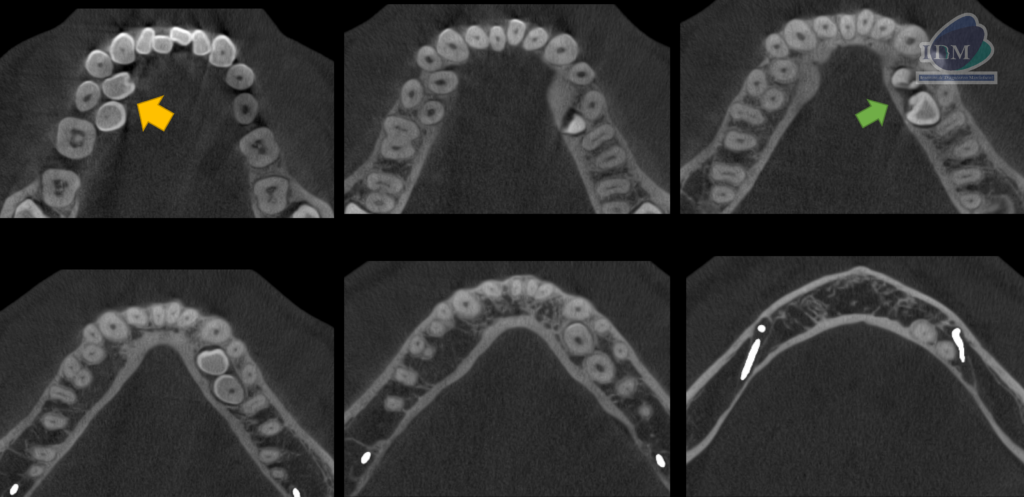

A la evaluación de la tomografía computarizada se puede observar la posición exacta de los cuatro supernumerarios mandibulares suplementarios, así como la relación con las piezas dentarias adyacentes y estructuras anatómicas importantes. Las flechas de color verde indican la posición del supernumerario A hacia lingual con la porción coronaria en contacto con la pieza 35 y el tercio apical en contacto con la cortical del conducto dentario inferior, así también el supernumerario B en estrecha relación con la superficie lingual de la pieza 34 (vista en cortes axiales, transaxiales y tangenciales).La flecha de color amarillo indican la localización por lingual de los supernumerios C Y D en estrecha relación con la superficie lingual de las piezas 44 y 45 respectivamente. En ambos cuadrantes se observa la giroversión y el desplazamiento hacia vestibular de las premolares.

CORTES AXIALES